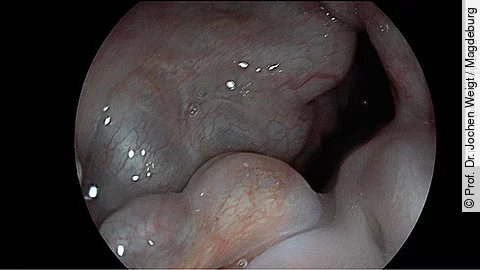

Darmkrebs ist in Deutschland häufig – aber durch Vorsorge vermeidbar. Die Deutsche Gesellschaft für Gastroenterologie, Verdauungs- und Stoffwechselkrankheiten (DGVS) erklärt, wie Stuhltest und Koloskopie Leben retten können und welche Methode sich wann eignet.